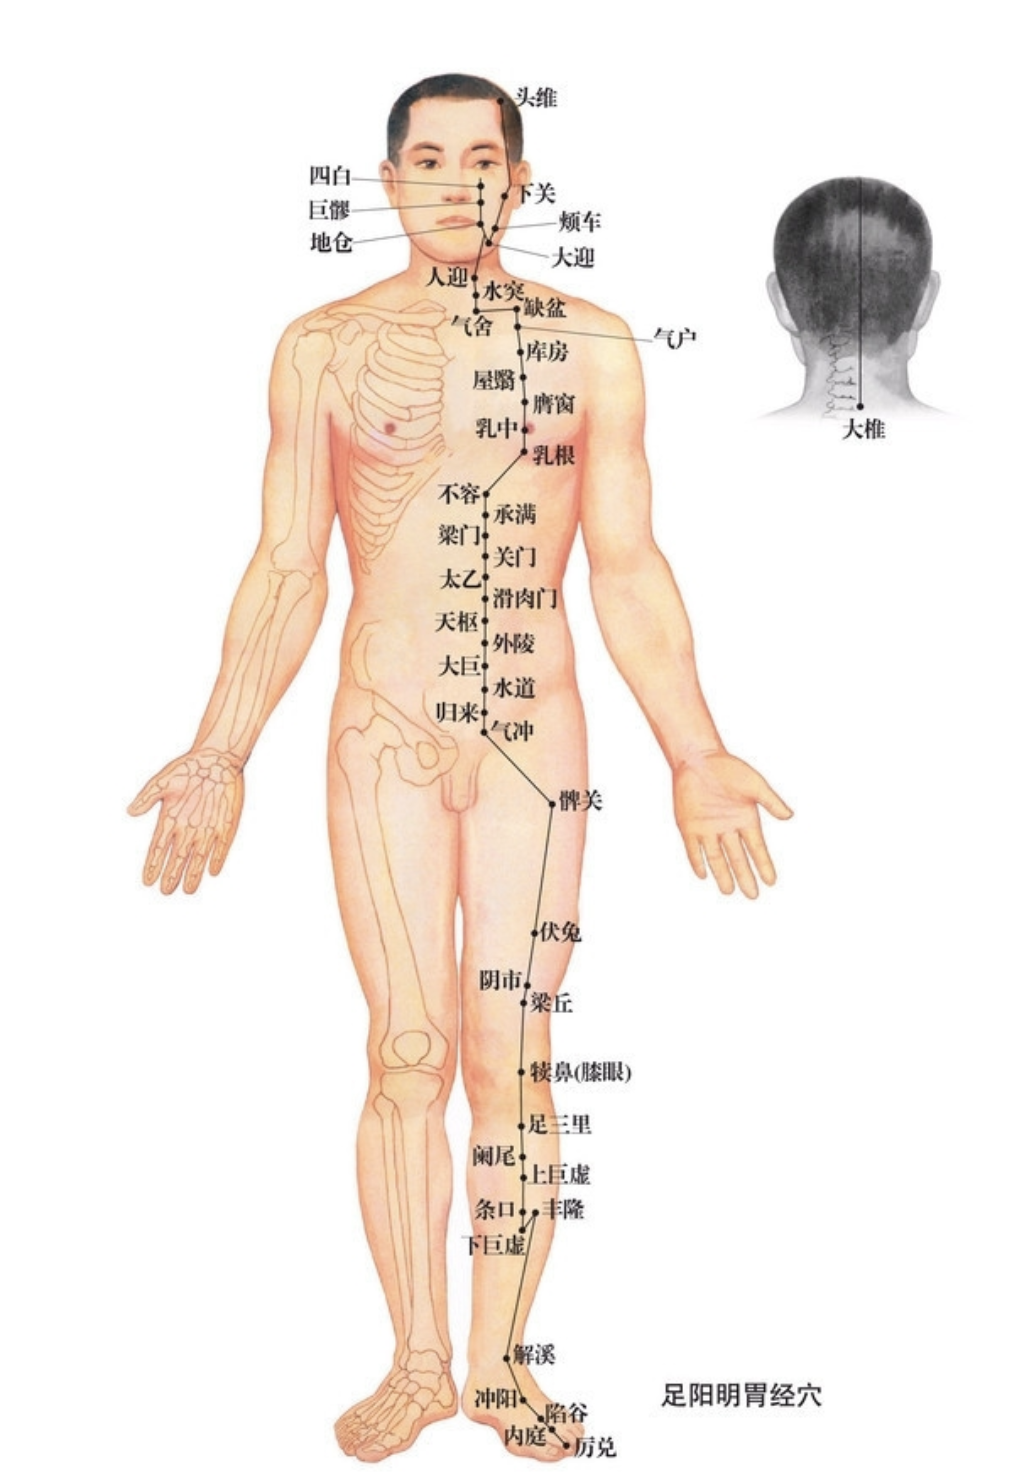

【(三)足阳明胃经(图10-21-1)】

图 10-21-1 足阳明胃经循行及常用腧穴

1、时辰 辰时 7 ~ 9

2、歌诀 四十五穴足阳明,承泣四白巨髎(liáo)经,地仓大迎下颊车,下关头维对人迎,水突气舍连缺盆,气户库房屋翳寻,膺窗乳中下乳根,不容承满出梁门,关门太乙滑肉起,天枢外陵大巨里,水道归来达气冲,髀关伏兔走阴市,梁丘犊鼻足三里,上巨虚连条口底,下巨虚下有丰隆,解溪冲阳陷谷同,内庭厉兑阳明穴,大趾次趾之端终。

3、经脉循行 起于鼻翼两侧(迎香),上行到鼻根部与足太阳经交会,向下沿鼻外侧进入上齿龈内,回出环绕口唇,向下交会于颏(kē)唇沟承浆处,再向后沿口腮后下方,出于下颌(hé)大迎处沿下颌角颊车,上行耳前,经上关,沿发际,到达前额(前庭)。

面部支脉:从大迎前下走人迎,沿着喉咙,进入缺盆部,向下过膈,属于胃,联络脾脏。

缺盆部直行的脉:经乳头,向下夹脐旁,进入少腹两侧气冲;

胃下口部支脉:沿着腹里向下到气冲会合,再由此下行至髀(bì)关,直抵伏兔部,下至膝盖,沿胫骨外侧前缘,下经足跗;进入第二足趾外侧端(厉兑)。

胫部支脉:从膝下 3 寸(足三里)处分出进入足中趾外侧端。

足跗部支脉:从跗上分出,进入足大趾内侧端(隐白)与足太阴脾经相接。

4、主要病候 肠鸣腹胀、水肿、胃痛、呕吐或消谷善饥、口渴、咽喉肿痛、鼻衄、胸部及膝髌(bìn)等本经循行部位疼痛、热病、发狂等。

5、主治概要 主治胃肠病、头面、目鼻、口齿痛、神志病及经脉循行部位的其他病证。

承泣

【定位】 在面部,瞳孔直下,当眼球与眶下缘之间。

【主治】 目赤肿痛,流泪,夜盲,眼睑瞤(rún)动,口眼歪斜。

【配伍】 配太阳治目赤肿痛,配阳白治口眼歪斜。

【刺灸法】 以左手拇指向上轻推眼球,紧靠眶缘缓慢直刺 0.5 ~ 1.5 寸,不宜提插,以防刺破血管引起血肿。

【附注】 足阳明经、阳跷、任脉交会处。

四白

【定位】 在面部,瞳孔直下,当眶下孔凹陷处。

【主治】 目赤痛痒,目翳,眼睑瞤(rún)动,口眼歪斜,头痛眩晕。

【配伍】 配阳白、地仓、颊车、合谷治口眼歪斜,配攒竹治眼睑瞤(rún)动。

【刺灸法】 直刺或斜刺 0.3 ~ 0.5 寸,不可深刺。

地仓

【定位】 在面部,口角旁约 0.4 寸,上直对瞳孔(图 10-21-2)。

【主治】 口歪,流涎,口角瞤(rún)动。

【配伍】 配颊车、合谷治口歪、流涎。

【刺灸法】 向颊车方向平刺 0.5 ~ 0.8 寸。

【附注】 手足阳明经、阳跷脉交会穴。

颊车

【定位】 在面颊部,下颌角前上方约 1 横指(中指),当咀嚼时咬肌隆起最高点,按之凹陷处。

【主治】 口歪,齿痛,颊肿,口噤不语。

【配伍】 配地仓治口眼歪斜。

【刺灸法】 直刺 0.3 ~ 0.5 寸,平刺 0.5 ~ 1 寸。

下关

【定位】 在面部耳前方,当颧弓与下颌切迹所形成的凹陷中(图 10-21-3)。

【主治】 耳聋,耳鸣,聤(tíng)耳,齿痛,口噤,口眼歪斜。

【配伍】 配翳风治耳疾。

【刺灸法】 直刺 0.5 ~ 1 寸。

【附注】 足阳明、足少阳经交会穴。

缺盆

【定位】 在锁骨上窝中央,距前正中线 4 寸。

【主治】 咳嗽,气喘,咽喉肿痛,缺盆中痛,瘰疬。

【配伍】 配肺俞治咳嗽。

【刺灸法】 直刺或斜刺 0.3 ~ 0.5 寸。

【附注】 《类经图翼》:孕妇禁针。

天枢

【定位】 在腹中部,平脐中,距脐中 2 寸。

【主治】 腹胀肠鸣,绕脐痛,便秘,泄泻,痢疾,月经不调。

【配伍】 配足三里治腹胀肠鸣,配气海治绕脐痛,配上巨虚、下巨虚治便秘、泄泻。

【刺灸法】 直刺 1 ~ 1.5 寸。

【附注】 (1)大肠的募穴。(2)《千金方》:孕妇不可灸。

梁丘

【定位】 屈膝,大腿前面,当髂(qià)前上棘(jí)与髌(bìn)骨外上缘的连线上,髌骨上缘 2 寸。

【主治】 膝肿痛,下肢不遂,胃痛,乳痈,血尿。

【配伍】 配足三里、中脘治胃痛。

【刺灸法】 直刺 1 ~ 1.2 寸。

【附注】 足阳明经郗(chī)穴。

足三里

【定位】 在小腿前外侧,当犊(dú)鼻下 3 寸,距胫骨前嵴(jí)外 1 横指(中指)(图 10-21-4)。

【主治】 胃痛,呕吐,噎(yē)膈,腹胀,泄泻,痢疾,便秘,乳痈,肠痈,下肢痹痛,水肿,癫狂,脚气,虚劳羸(léi)瘦。

【配伍】 配中脘、梁丘治胃痛,配内关治呕吐,配气海治腹胀,配膻中、乳根治乳痈,配阳陵泉、悬钟治下肢痹痛,常灸足三里可养生保健。

【刺灸法】 直刺 1 ~ 2 寸,强身健体用灸法。

【附注】 (1)足阳明经所入为“合”;胃的下合穴。(2)本穴有强壮作用,为保健要穴。(3)参考资料:①据报道,针刺健康人和胃病患者的足三里和手三里,观察发现胃驰缓时针刺收缩加强,胃紧张时变为弛缓,并可解除幽门痉挛。②据报道,针刺单纯性消化不良和中毒性消化不良患儿的足三里、合谷、三阴交,可使原来低下的胃游离酸、总酸度、胃蛋白酶和胃脂肪酶活性迅速升高。③据报道,针刺人及家兔的足三里,发现裂解素(主要是裂解素含有大量多糖体的革兰氏阴性杆菌,也能灭活某些病毒)都有增加,人增加 17.85 单位,兔增加 62.1 单位,两者均在针后 12 小时增加最明显。④据报道,针刺家兔的“足三里”“大椎”可使其调理素明显增加,从而促进白细胞吞噬指数的上升,增强其免疫能力。

丰隆

【定位】 在小腿前外侧,当外踝尖上 8 寸,条口外 1 寸,距胫骨前嵴外 2 横指(中指)(图 10-21-4)。

【主治】 头痛,眩晕,痰多咳嗽,呕吐,便秘,水肿,癫狂,痫症,下肢痿痹。

【配伍】 配风池治眩晕,配膻中、肺俞治痰多咳嗽。

【刺灸法】 直刺 1 ~ 1.5 寸。

【附注】 足阳明经络穴。

厉兑

【定位】 在足第 2 趾末节外侧,距趾甲角 0.1 寸。

【主治】 鼻衄,齿痛,咽喉肿痛,腹胀,热病,多梦,癫狂。

【配伍】 配内关、神门治多梦。

【刺灸法】 浅刺 0.1 寸。

【附注】 足阳明经所出为“井”。